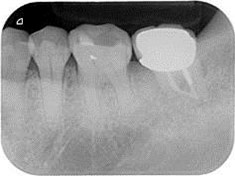

牙周初診時患者之口內觀。口內明顯牙菌斑及牙結石堆積。全口嚴重牙齦紅腫。治療前X光片。#37的近心側有較深的骨內缺損,剩餘齒槽骨高度只有20%。

A圖為#37根管治療完後的三個月放射線攝影根尖片。